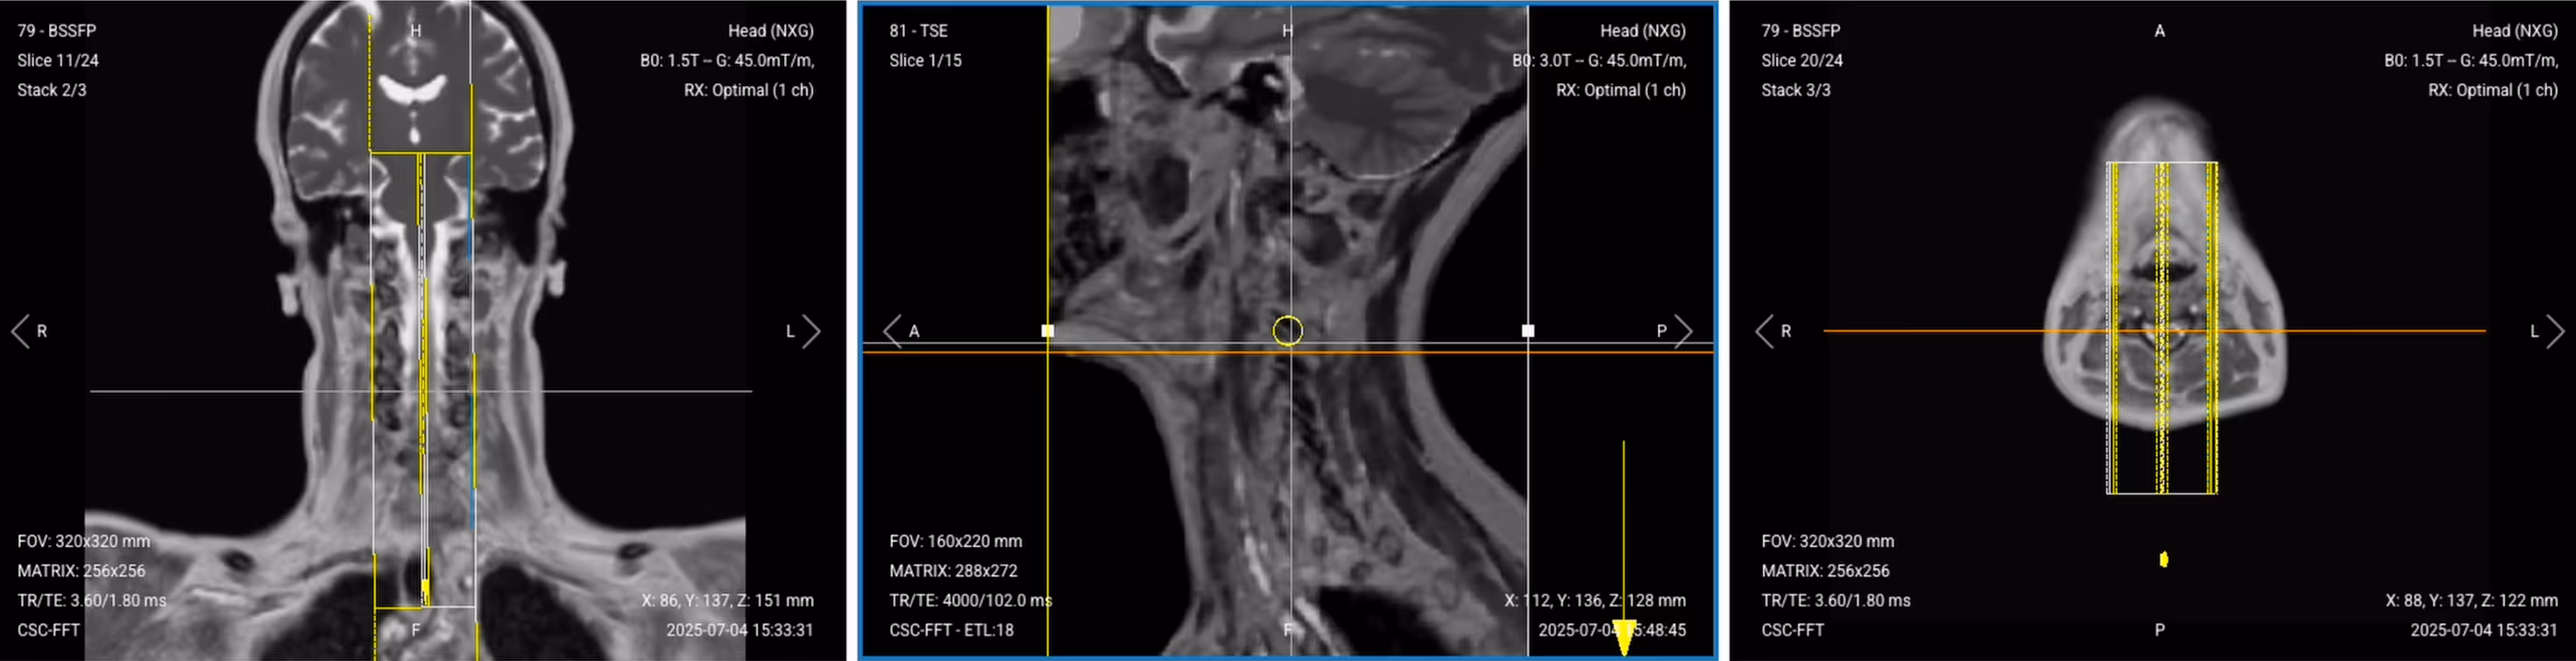

3. Capture the Initial Localizer Images

Before we can perform any MRI protocol, we must always capture initial localizer images of the patient. These images act as a guide for planning the detailed scans we will perform next.

We should always capture localizers in three planes:

1. Axial

2. Sagittal

3. Coronal

Once acquired, upload the initial localizer images into the three viewports.

Then, scroll through each of the image stacks to locate a central slice that clearly shows the anatomy of the cervical spine.

Correct Setup of Localizer Images for Cervical Spine MRI:

Correct setup of localizer images for Cervical Spine MRI